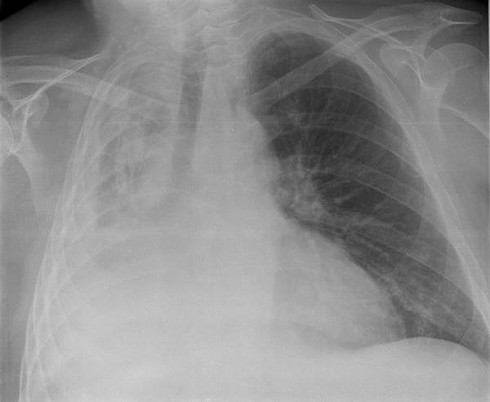

Hình chụp X-quang của một người bị sụp phổi. Ảnh: SCMP |

Một người đàn ông 65 tuổi đến từ miền đông Trung Quốc cần phải nhập viện vì sập phổi (tràn màn khí phổi) sau một buổi hát karaoke dài bất thường, báo South China Morning Post đưa tin.

Sau khi đến bệnh viện, bác sĩ Peng Bin-fei tại bệnh viện Nanchang nói rằng ông Wang đã bị sụp phổi, hày còn được gọi là tràn khí màng phổi, và cho biết chính những bài hát cao đã gây nên tình trạng trên.

Tràn khí màng phổi là khi có một lượng không khí bất thường trong khoang màng phổi giữa phổi và thành ngực. Các triệu chứng thường bao gồm đột ngột đau nhói, đau một bên ngực và khó thở. Trong một số ít trường hợp, lượng không khí trong ngực tăng lên khi van một chiều được hình thành bởi một vùng mô bị tổn thương, dẫn đến tràn khí màng phổi căng.